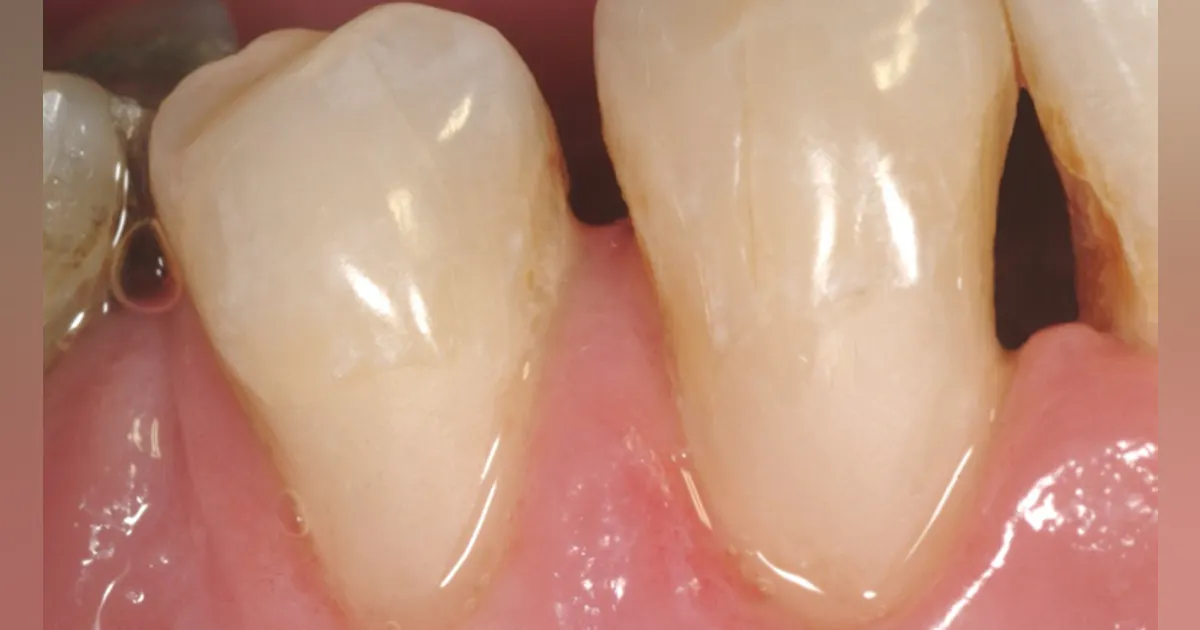

Would it not be better to place a composite resin restoration on the tooth? That procedure poses little threat to the dental pulp. It allows retention of much more tooth structure than a crown prep, and it costs less than a crown. Well-done composite restorations can easily match tooth color, while an anterior crown is difficult to match to surrounding tooth structure. A crown can always be done years later allowing the resin restoration to serve in the interim. According to our surveys, the most popular products for this procedure are Filtek Supreme Ultra, TPH Spectra, and Harmonize. These and numerous others provide excellent color match and at least several years of service (figure 3).